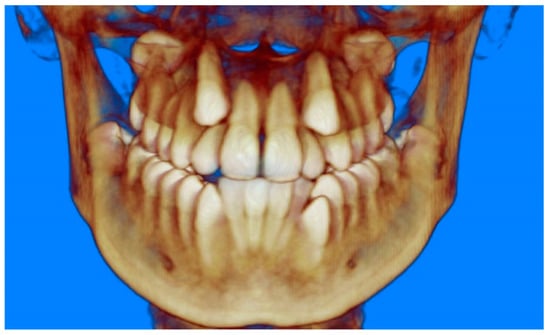

- Evaluation of impacted teeth, a common indication of CBCT in orthodontics. The advantages of CBCT include assessment of the tooth location and position, the stage of development, and status of adjacent teeth. CBCT is justified in these cases, because CBCT has the capability of evaluating the impacted teeth and adjacent structures more accurately than 2D conventional imaging. The benefit–risk ratio is favorable, especially if the CBCT volume is collimated to the impacted tooth. Figure 1, Figure 2, Figure 3 and Figure 4 show an example of impacted maxillary canines, and their proximity to the maxillary lateral incisors. Figure 1 shows an intraoral photograph. The benefit of CBCT acquisition in this case includes the ability to visualize the canines and the lateral incisors in three dimensions, which can be visualized in Figure 2 and Figure 3. In this case, the maxillary right lateral incisor exhibited external root resorption, a finding that would be difficult to see on a conventional 2D panoramic radiograph. Figure 4 shows a Maximum Intensity Projection of a panoramic view derived from the CBCT volume. This unique view is free of magnification, distortion, ghost images, and overlaps frequently seen in conventional 2D panoramic radiography.